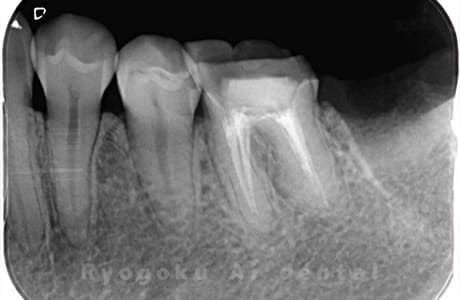

他院で右下の根の治療を行い、セラミックを被せる説明をされていたが、根の治療が終わらないため転院された患者さんです。隣の親知らずの抜歯の必要性と、根の治療を行なっている歯牙の予後が悪いため、移植治療を提案し、右下の親知らずの抜歯と同時に、右下の奥歯(7番)への移植治療を行いました。被せ物を行う必要もなく、順調に経過してます。